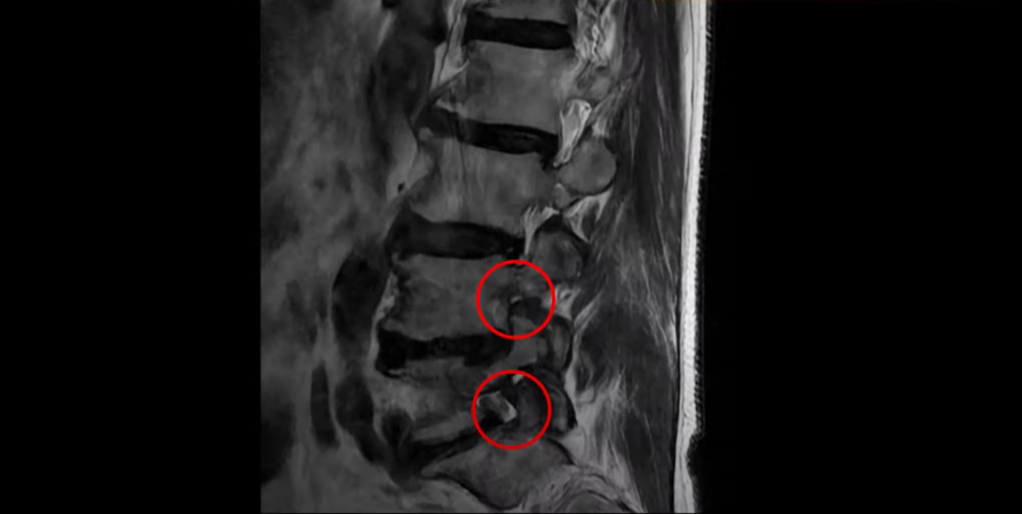

협착증은 노화 때문에 생기는 질환입니다. 나이가 들수록 노화와 퇴행 때문에 신경 구멍이 조금씩 좁아집니다. 이분도 신경 구멍이 좁아져 있습니다. 보시다시피 척추 여러 마디가 퇴행되어 있고

특히 왼쪽 신경가지가 빠져나가는 추간공들이 많이 좁아져 있습니다.

이분은 약 한달 전에 갑자기 왼쪽 다리를 아예 못 쓸 만큼 심하게 아프게 되었는데 허리를 펼 수도 없고 몇 미터 걸을 수도 없는 상태였습니다. 신경 주사를 여러 대 맞아도 전혀 듣지 않는 상태였는데 이분처럼 MRI 검사에서 신경구멍이 좁아져 있고 신경주사가 아예 듣지 않으면 십중팔구 수술하자는 얘기를 듣게 됩니다.